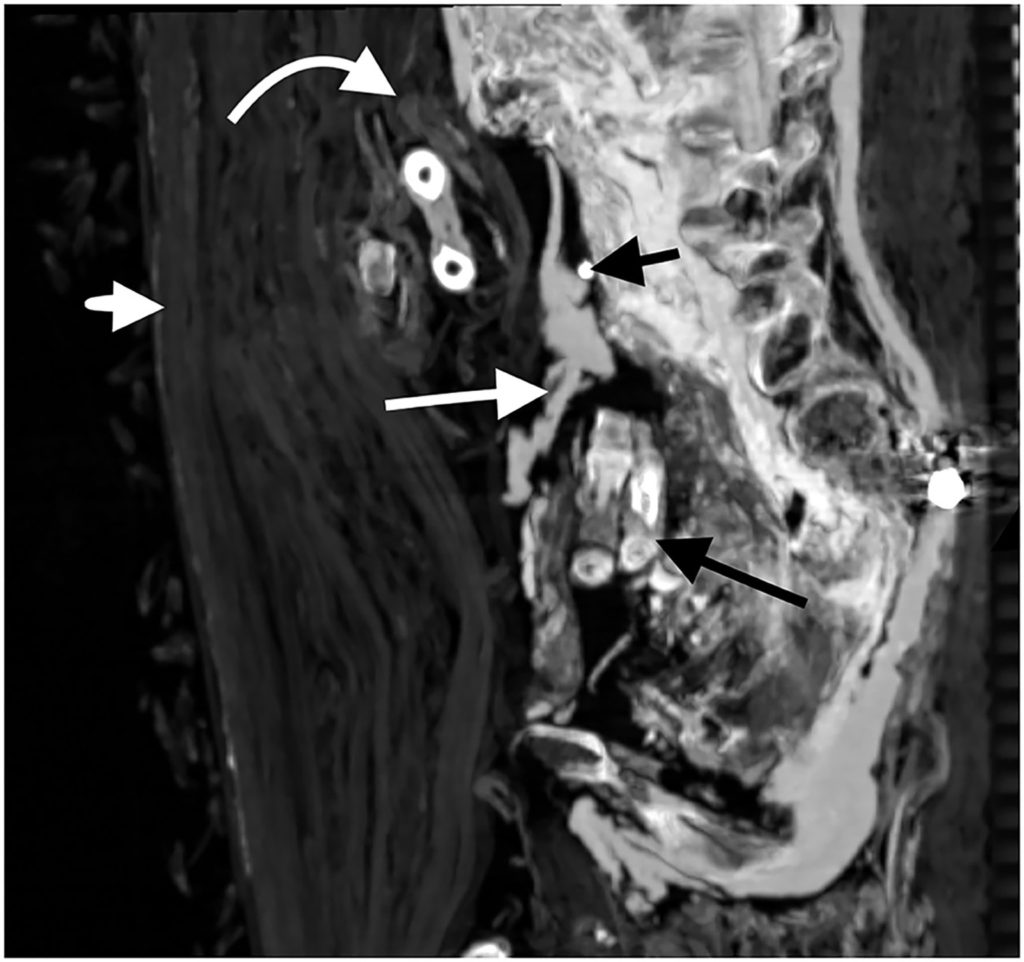

Computed tomography (CT) technology, which creates a cross-section of a body using X-rays, revealed the pharaoh’s face and a chest full of treasure, including 30 amulets and “a unique golden girdle with gold beads,” study co-author Sahar Saleem said in a statement. The findings were published Tuesday in the journal Frontiers in Medicine.

“By digitally unwrapping the mummy and ‘peeling off’ [the layers around the body] — the face mask, the bandages and the mummy itself — we could study this well-preserved pharaoh in unprecedented detail,” Saleem, a radiology professor at Cairo University’s school of medicine, added.